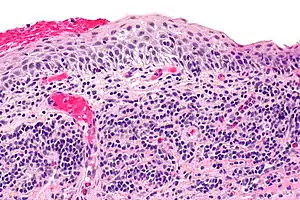

| Micrograph of plasmacytosis mucosae. H&E stain. | |

Balanitis plasmacellularis is a skin condition characterized by a benign inflammatory skin lesion characterized histologically by a plasma cell infiltrate.[1][2]: 657 [3]